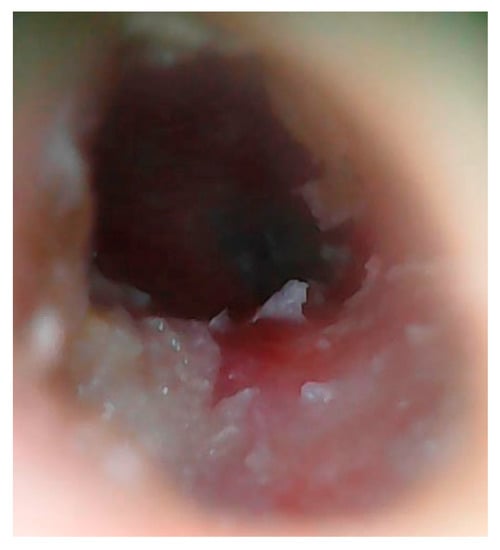

3.1. Patient 1

3.2. Patient 2

3.3. Patient 3